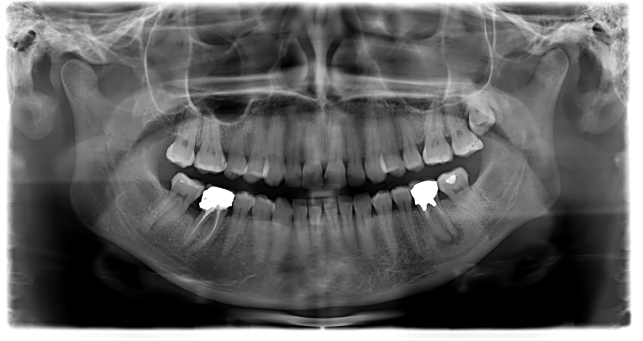

L’indagine è eseguita mediante una apparecchiatura radiografica denominata Ortopantomografo con una tecnica radiografica denominata Tomografia ed evidenzia l’immagine delle Arcate Dentarie, dei Denti, delle Ossa Mascellari, della Mandibola, dei Seni Mascellari, del Canale del Nervo Mandibolare e delle Articolazioni Temporo-Mandibolari.

L’Ortopantomografia è utilizzata nell’ambito odontoiatrico e medico poichè permette di  evidenziare patologie delle Arcate Dentarie, quali: Denti Inclusi, Cisti Mandibolari e Mascellari,  Granulomi, Parodontopatie, Fratture dei Denti, fratture dei Mascellari; permette inoltre di evidenziare la presenza di tutti gli Elementi Dentari, la loro Forma e Posizione, la presenza di Carie Interdentale e di Carie al di sotto di otturazioni pregresse difficili da diagnosticare.